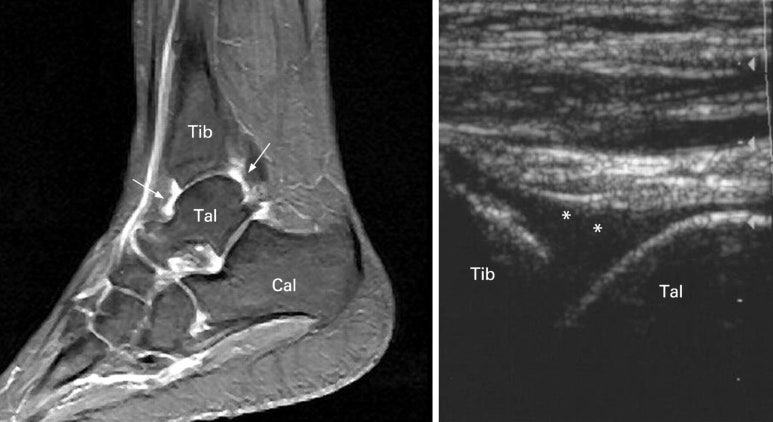

발목 관절낭염의 MRI, 초음파 이미지

하지만

위 그림처럼

관절낭염이 동반된 경우는

3주 이상 불편감이 지속되고,

괜찮아지는것 같다가도

피곤하거나

비가 온다거나

많이 걸으면

금방 재발됩니다.